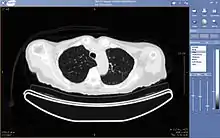

Picture archiving and communication system

A picture archiving and communication system (PACS) is a medical imaging technology which provides economical storage and convenient access to images from multiple modalities (source machine types).[1] Electronic images and reports are transmitted digitally via PACS; this eliminates the need to manually file, retrieve, or transport film jackets, the folders used to store and protect X-ray film. The universal format for PACS image storage and transfer is DICOM (Digital Imaging and Communications in Medicine). Non-image data, such as scanned documents, may be incorporated using consumer industry standard formats like PDF (Portable Document Format), once encapsulated in DICOM. A PACS consists of four major components: The imaging modalities such as X-ray plain film (PF), computed tomography (CT) and magnetic resonance imaging (MRI), a secured network for the transmission of patient information, workstations for interpreting and reviewing images, and archives for the storage and retrieval of images and reports. Combined with available and emerging web technology, PACS has the ability to deliver timely and efficient access to images, interpretations, and related data. PACS reduces the physical and time barriers associated with traditional film-based image retrieval, distribution, and display.

Most PACS handle images from various medical imaging instruments, including ultrasound (US), magnetic resonance (MR), Nuclear Medicine imaging, positron emission tomography (PET), computed tomography (CT), endoscopy (ES), mammograms (MG), digital radiography (DR), phosphor plate radiography, Histopathology, ophthalmology, etc. Additional types of image formats are always being added. Clinical areas beyond radiology; cardiology, oncology, gastroenterology, and even the laboratory are creating medical images that can be incorporated into PACS. (see DICOM Application areas).